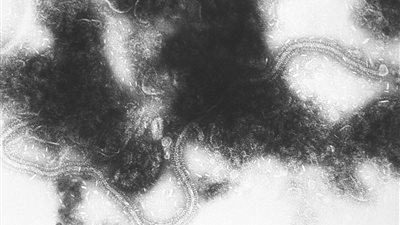

الفيروس المخلوي التنفسي صفحة 2

الفيروس المخلوي التنفسي.. مرض غامض يسبب ذعرًا لـ المواطنين وينتشر بين الأطفال | القصة كاملة